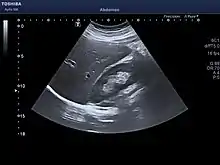

The diagnosis of liver disease is made by liver function tests, groups of blood tests, that can readily show the extent of liver damage. If infection is suspected, then other serological tests will be carried out. A physical examination of the liver can only reveal its size and any tenderness, and some form of imaging such as an ultrasound or CT scan may also be needed.

Sometimes a liver biopsy will be necessary, and a tissue sample is taken through a needle inserted into the skin just below the rib cage. This procedure may be helped by a sonographer providing ultrasound guidance to an interventional radiologist.[65]

Microscopically, each liver lobe is seen to be made up of hepatic lobules. The lobules are roughly hexagonal, and consist of plates of hepatocytes, and sinusoids radiating from a central vein towards an imaginary perimeter of interlobular portal triads.[22] The central vein joins to the hepatic vein to carry blood out from the liver. A distinctive component of a lobule is the portal triad, which can be found running along each of the lobule's corners. The portal triad consists of the hepatic artery, the portal vein, and the common bile duct.[23] The triad may be seen on a liver ultrasound, as a Mickey Mouse sign with the portal vein as the head, and the hepatic artery, and the common bile duct as the ears.[24]